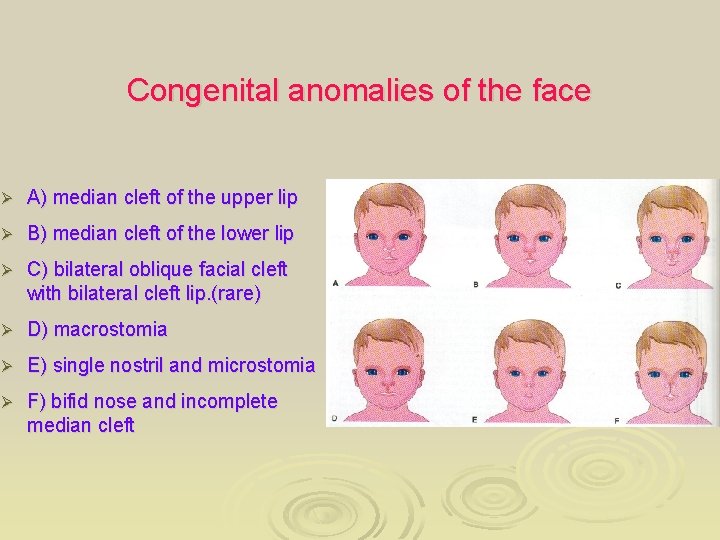

Congenital anomalies of the face Ø A) median cleft of the upper lip Ø B) median cleft of the lower lip Ø C) bilateral oblique facial cleft with bilateral cleft lip. (rare) Ø D) macrostomia Ø E) single nostril and microstomia Ø F) bifid nose and incomplete median cleft